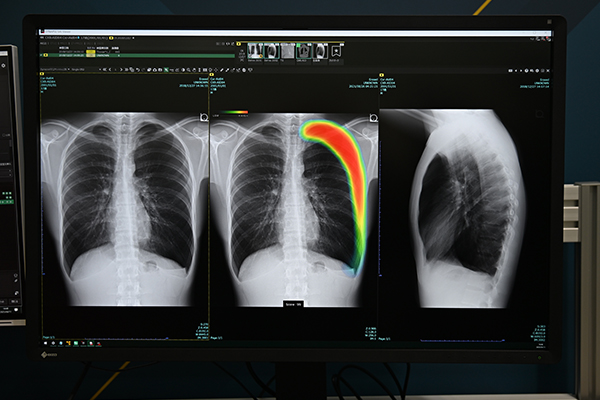

EIZOは,“Making Each Life Visual”というキーメッセージの下,プレシジョン・メディシンで重要となる情報を映し出すモニター製品とその品質管理のためのソフトウエア,ツールを来場者にアピールした。2024年7月8日に厚生労働省告示で,「GSDFキャリブレーション機能付き画像診断用ディスプレイ」が一般医療機器となり,特定保守管理医療機器に指定された。同社はこれに速やかに対応して,国内初の特定保守管理医療機器となる画像診断用モニター「RadiForce RX370DD」を2024年10月に発表した。階調特性をGSDFに準拠するように調整された上で出荷される。導入後は,内蔵センサと品質管理ソフトウエア「RadiCS」でキャリブレーションを行うことで,表示性能を適切に管理できる。その後,さらに5メガピクセルの「RadiForce RX570DD」を11月に発表。2025年3月には7機種を追加し,現在,9機種の特定保守管理医療機器の画像診断用モニターをラインアップしている。

国内初の特定保守管理医療機器となる画像診断用モニター「RadiForce RX370DD」

「RadiForce RX370DD」は内蔵センサと

品質管理ソフトウエア「RadiCS」によるキャリブレーションが可能